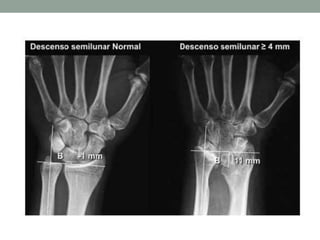

Diagnóstico Imagenológico

• McCarroll et al. 2010

• Tilt ulnar

• Subsidencia del semilunar ≥ 4mm

• Distancia entre la perpendicular al eje

de la ulna y el polo proximal del

semilunar

• Angulo de laa fosa semilunar

• Desplazamiento volar del carpo

Diagnóstico Imagenológico • McCarrollet al. 2010 • Tilt ulnar • Subsidencia del semilunar ≥ 4mm • Distancia entre la perpendicular al eje de la ulna y el polo proximal del semilunar • Angulo de laa fosa semilunar • Desplazamiento volar del carpo